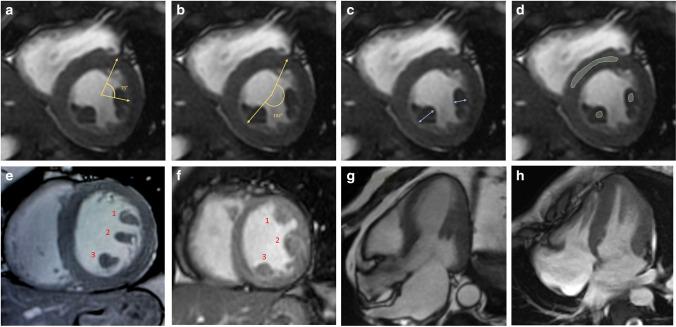

A total of 391 patients with > 500/24 h premature ventricular complexes and/or with non-sustained ventricular tachycardia (NSVT), preserved LVEF, and no cardiac disease were enrolled. Different features of LV papillary muscles were considered: supernumerary muscles, papillary thickness, the attachment, late gadolinium enhancement (LGE). Dark-Paps was defined as end-systolic signal hypointensity of both papillary muscles in early post-contrast cine CMR images. Mitral valve prolapse, mitral annular disjunction (MAD), and myocardial LGE were considered.

Dark-Paps was found in 79 (20%) patients and was more frequent in females. It was associated with higher prevalence of mitral valve prolapse and MAD. During a median follow-up of 2534 days, 22 hard cardiac events occurred. At Kaplan-Meier curve analysis, patients with Dark-Paps were at higher risk of events than those without (p < 0.0001). Dark-Paps was significantly associated with hard cardiac events in all the multivariate models. Dark-Paps improved prognostic estimation when added to NSVT (p = 0.0006), to LGE (p = 0.005) and to a model including NSVT+LGE (p = 0.014). Dark-Paps allowed a significant net reclassification when added to NSVT (NRI 0.30, p = 0.03), to LGE (NRI 0.25, p = 0.04), and to NSVT + LGE (NRI 0.32, p = 0.02).

• Papillary muscle abnormalities are seen in patients with ventricular arrhythmias and preserved left ventricular ejection fraction. • Early post-contrast hypointensity of papillary muscles in end-systolic cine images (Dark-Paps) is a novel prognostic marker in patients with ventricular arrhythmias and preserved ejection fraction. • Dark-Paps had an additive prognostic role over late gadolinium enhancement and non-sustained ventricular tachycardia.